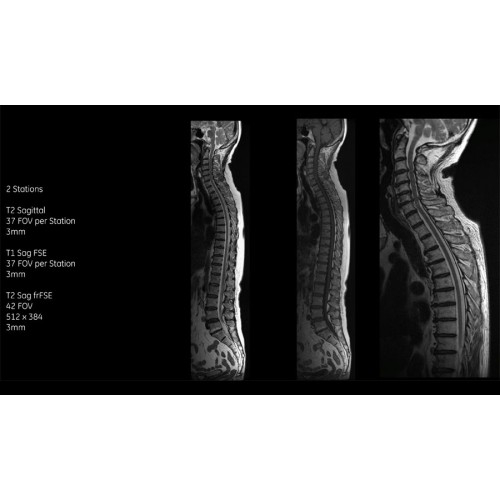

Система SIGNA Pioneer воплощает поразительные достижения в области визуализации. Передовая технология Total Digital Imaging (TDI) позволяет добиться большей четкости изображений и на четверть повысить соотношение сигнал/шум.

• Технология Digital Surround Technology (DST) — это новая технология объемной оцифровки данных, объединяющая сигналы от каждого элемента катушки. Прекрасное соотношение сигнал/шум и чувствительность поверхностных катушек в сочетании с превосходной однородностью и высокой проникающей способностью встроенной радиочастотной катушки — все это позволяет создавать качественные изображения не только позвоночника, но и всего тела.

Помимо технологии 97 РЧ-каналов, SIGNA Pioneer использует магнит 3.0Т высокой однородности, предназначенный для повышения качества визуализации во всех областях, а также закладывающий прочный фундамент для долгосрочных инвестиций и роста клинических возможностей.